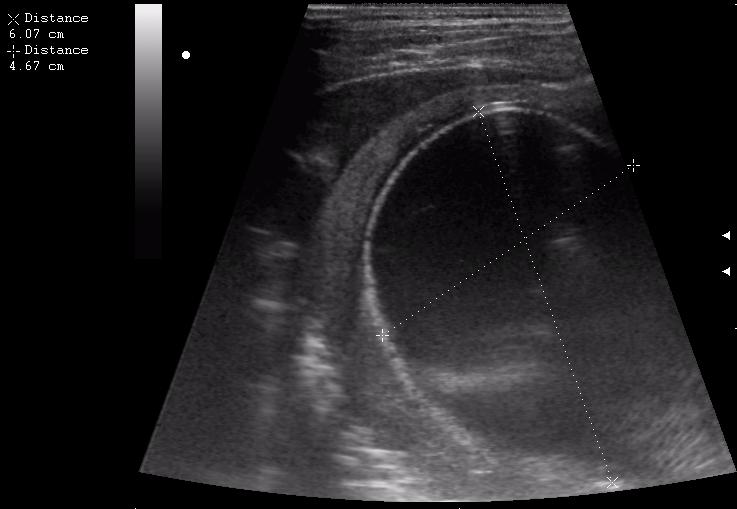

эхинококкоз печени девочка 12 лет.

живой эхинококк.